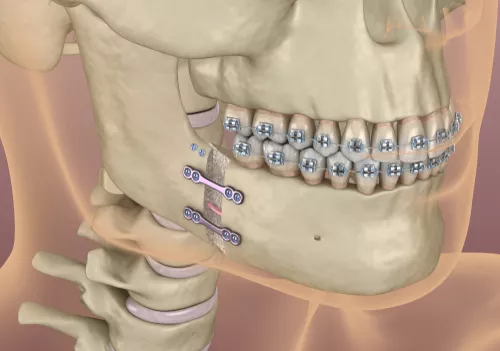

כירורגיה אורתוגנטית

הכירורגיה האורתוגנטית זו שיטה טיפולית הנעזרת בניתוח לצורך תיקון היחס הבין לסתי. כאשר לסת אחת בולטת מאוד לעומת השניה או כאשר לסת אחת צרה מאוד לעומת השניה.